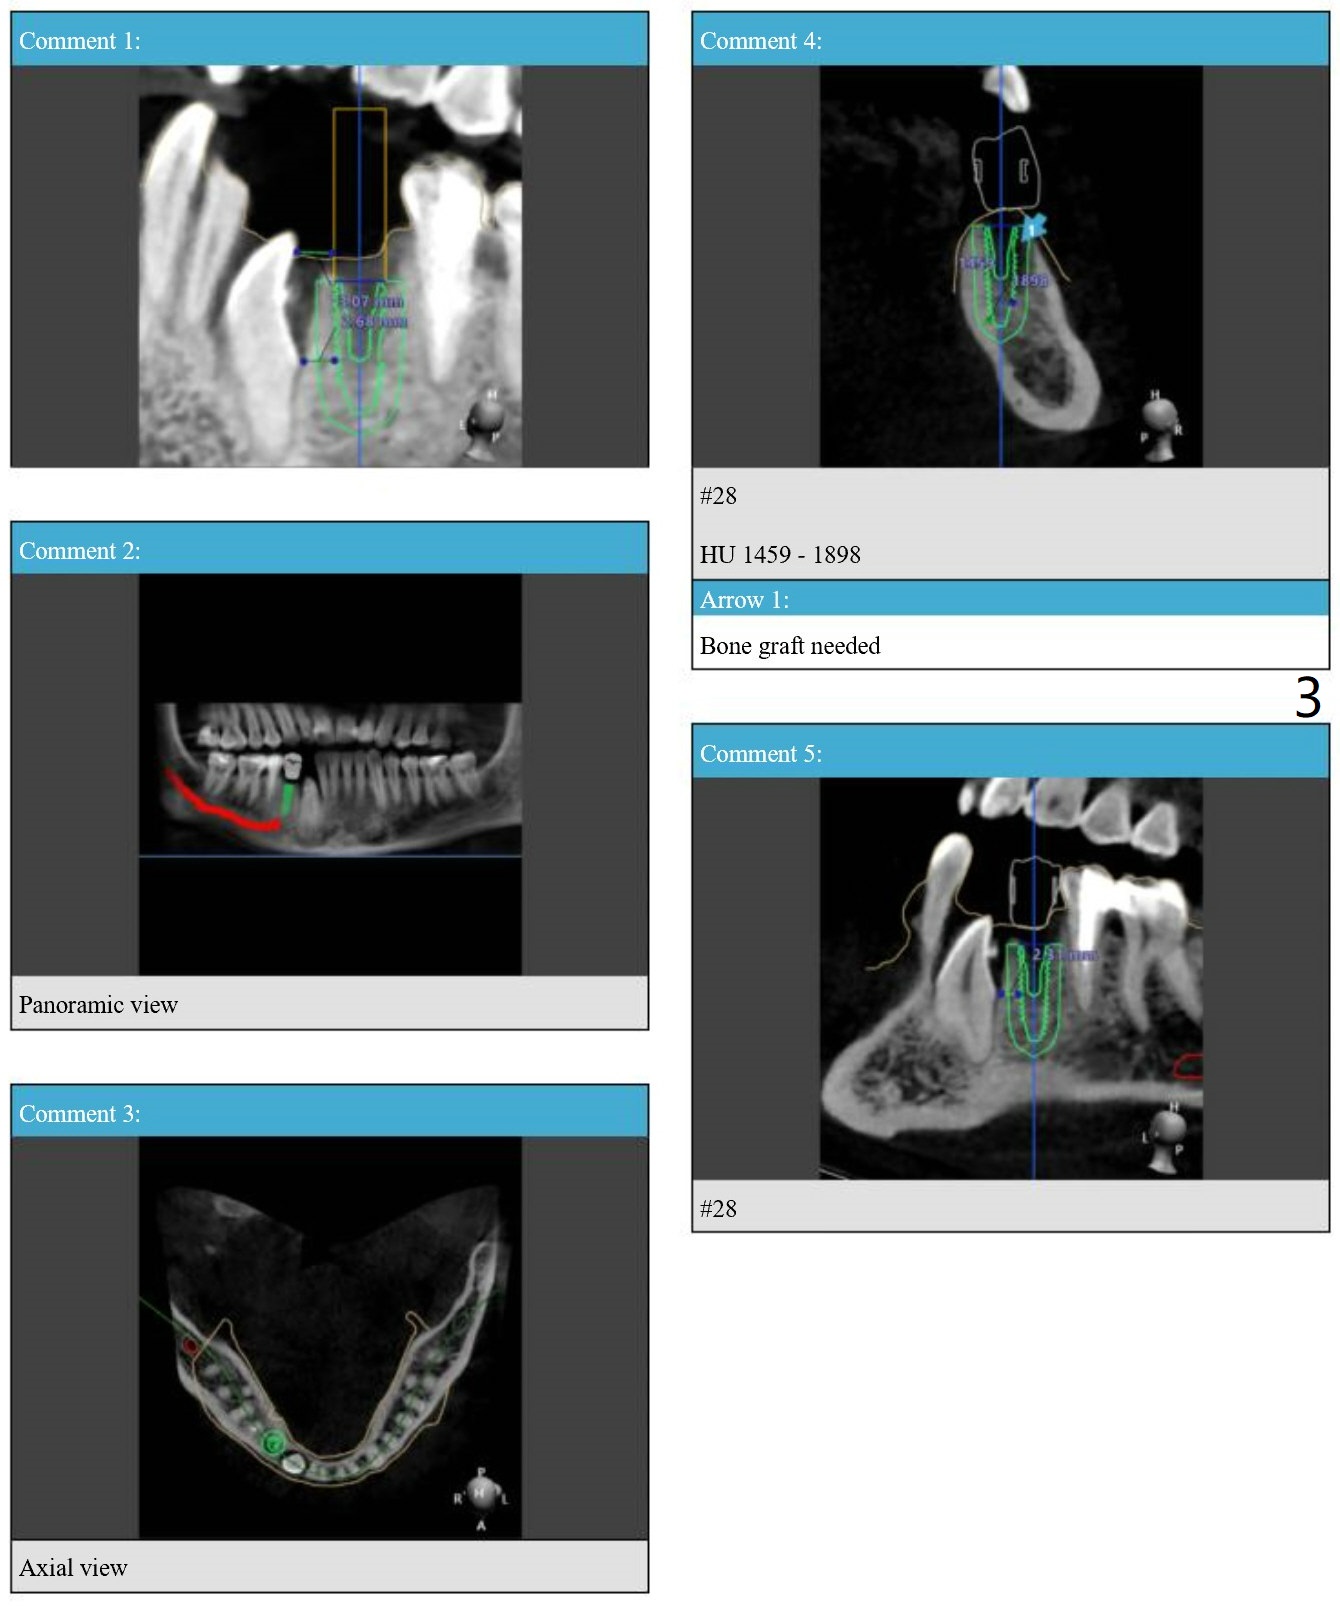

A 30-year-old man had the tooth #28 extracted with no bone graft. Allograft will be placed post implantation.

Lower Premolar

Immediate Implant,

Trajectory